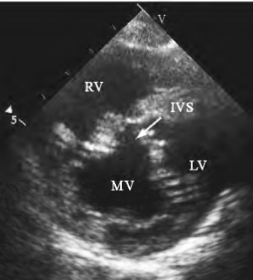

(2)左室二尖瓣口短轴切面,显示前后瓣叶及交界处不能完全闭合(图13-6)。轻度关闭不全时前外或后内交界小范围闭合不良;重度关闭不全时瓣叶部分或全部不能闭合。

图13-6 二尖瓣关闭不全二维超声图

二尖瓣口短轴切面,显示收缩期瓣口交界处闭合不良(箭头所示)